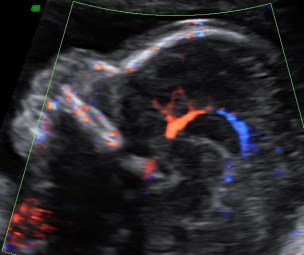

L’ecografia del secondo trimestre, meglio conosciuta come ecografia morfologica, è il massimo concentrato delle potenzialità dello studio ecografico: questa è l’epoca gestazione in cui si ha il miglior rapporto tra le dimensioni del feto stesso e la risoluzione dell’apparecchio, al fine di eseguire un’analisi morfostrutturale. Si possono investigare estensivamente parametri della crescita e del benessere fetale, implementando lo studio con la visualizzazione e valutazione della vascolarizzazione fetale ed uterina. Una profonda conoscenza dell’anatomia fetale permette inoltre di realizzare un’ecografia genetica, valutando il rischio di patologie cromosomiche.